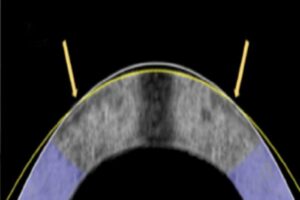

The electromechanical reshaping technique successfully flattened this rabbit cornea, shown in cross section, from its original shape (white line) to its corrected shape (yellow line).

An Alternative To LASIK Without The Lasers